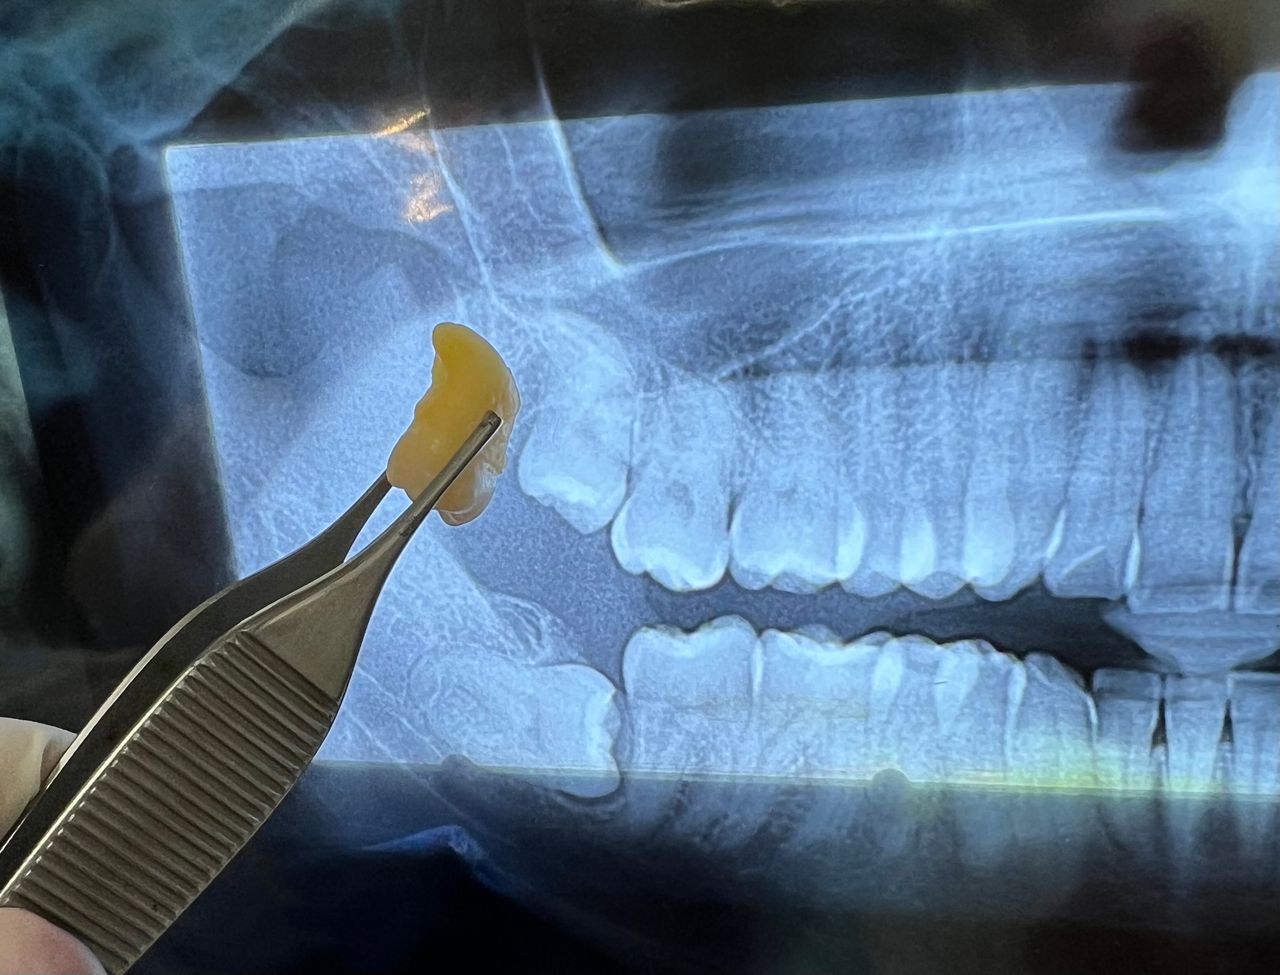

Restauraciones Adhesivas o Incrustaciones dentales

Cirugía de muela del juicio

Cirugía de diente retenido

Cirugia del tercer molar

Extracción dental

Extracción de otras piezas dentarias

Extracción de las muelas del juicio